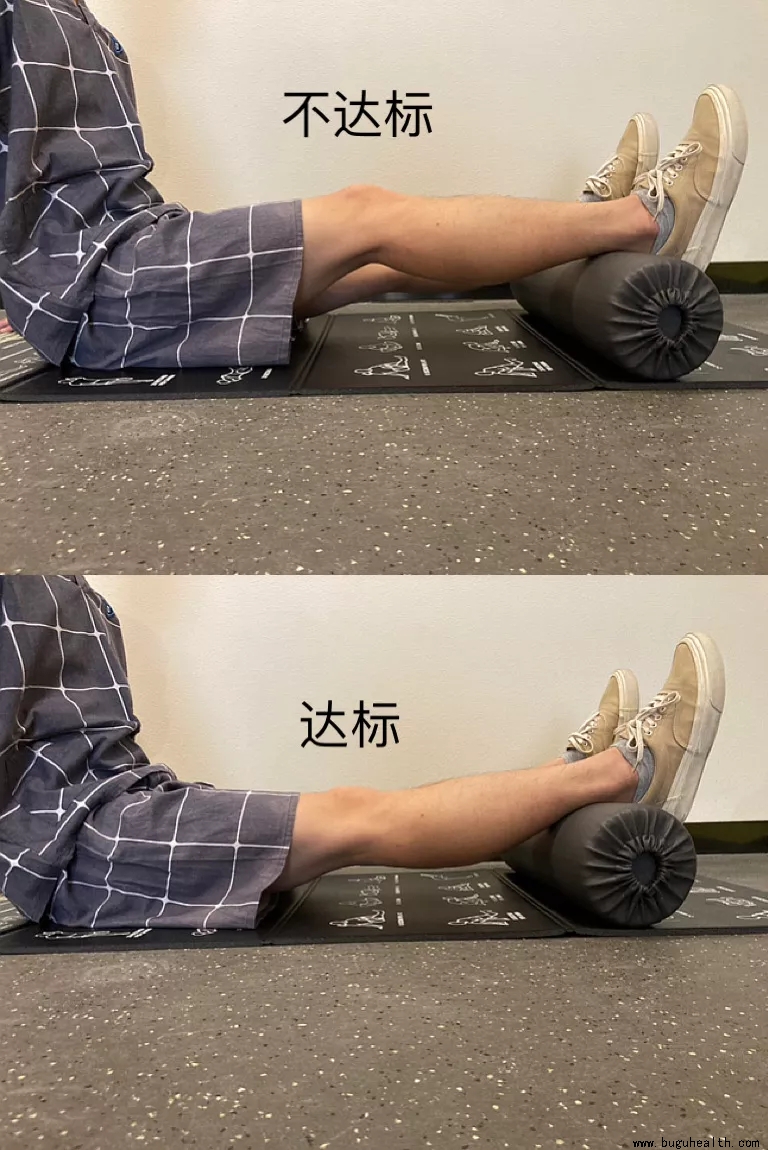

- 在膝关节手术之后,也许你进行的第一项维持你肌力的康复训练方法就是直抬腿,动作十分简单:伸直你的膝盖,然后向上抬离床面,保持3-5秒放下即可。但就是这个动作,你能确保你是做对的吗?如果感到怀疑,来做以下动作来进行实验:首先在测试前,我们需要先排除你的膝关节伸直功能没有受限,排除的方法是:膝关节伸直并且.....

- 上一篇文章呢,给大家介绍了一些方法,帮助我们在术后早期被动的或在辅助之下达到正常的伸直角度。那么在被动的膝关节伸直角度达到之后,还有一件更重要的事,那就是主动伸直的训练,同时也是股四头肌的激活训练。只有这样,才能把重新获得的伸直角度牢牢的保持住,才能保证不再反弹。 .....

- 布骨医学科普:4个动作,帮你解决膝关节伸不直 布骨康复医疗中心 ,2021-11-09

- 上一次跟大家分享了膝关节术后早期伸直的重要性,希望大家都能尽早重视这个指标,防止因为它影响了自己后期的恢复进度。今天呢,我们来分享一下如果你发现自己膝关节伸不直,如何去尝试解决它。.....

- 前交叉韧带重建术后早期最重要的两件事:1.能够完全伸直膝关节;2.激活股四头肌。如果你术后早期就注意这两个问题,这一点都不难,很轻松就可以达到。但如果很不巧,你在早期这两个方面没恢复好的话,后期会非常的麻烦。而且更重要的是,这两者之间是紧密联系的,往往一个不好,另外一个也就不好。.....